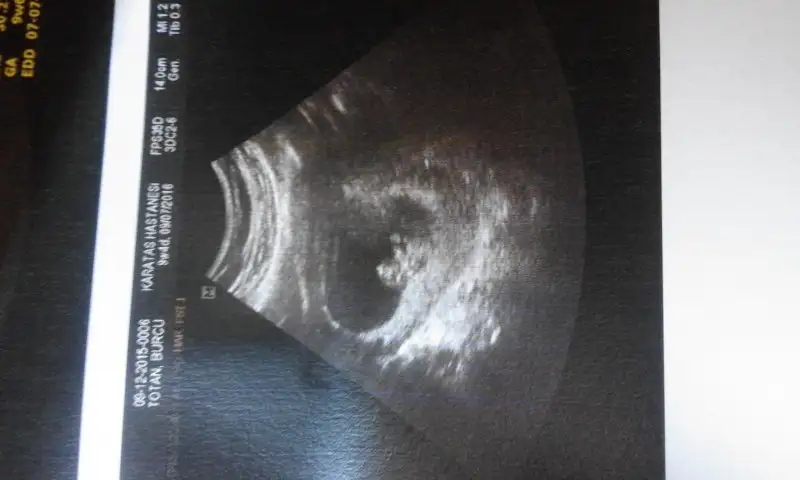

Resim çıkmamış dur ekliyim :)ceylaan1988 bu msj da plasentayı bulabilmen için bir resim var. Ondan yararlanabilirsin canım

Resim çıkmamış dur ekliyim :)

merhaba cnm.tesadüfen buradayım.paylaşımın çok ilginç geldi rica etsem benim usg görüntülerümi de yorumlar mısın?..2 farklı dr un,3 gün arayla muayenesi.birine göre 7+1 haftalık görünüyorum.diğerne göre 8+0 sata göre ise 8+2 olamlıydım o gün..Kesenin sağda veya solda olması önemli değil canım kesenin etrafını saran hale gibi beyaz renkli alan yani plasentanın konumuna göre cinsiyet tahmini yapmışlar.

rica etsem yukarıda yüklediğim ultrason fotolarını yorumlar mısınız?dlrsordn adlı arkadaşta adres vardı. ben baktım ama adresi unuttum. oraya girdiğinde tarih kısmına bebeğin olduğunu düşündüğün tarihi yazıp saat bölümünü +2 atina, istanbul yazan konuma getirip enter a basıyor muhtemel cinsiyeti söylüyor.